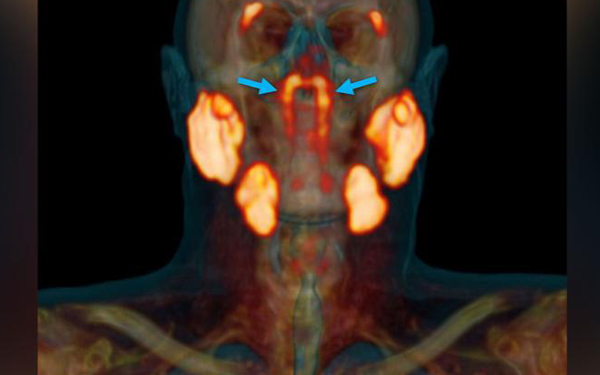

নেদারল্যান্ডসের বিজ্ঞানীরা জানান, তারা আগে উপেক্ষিত গ্রন্থিগুলোর একটি জোড়া আবিষ্কার করেছেন, যা মানুষের খুলিতে লুকিয়ে আছে, যেখানে অনুনাসিক গহ্বর এবং গলা মিলিত হয়েছে। চিকিৎসক গবেষকরা গ্রন্থিগুলোকে ‘টিউবারিয়াল লালা গ্রন্থি’ হিসেবে নামকরণের প্রস্তাব দেন।

নেদারল্যান্ডসের ক্যান্সার ইনস্টিটিউটের অ্যানকোলজি এবং সার্জারি বিভাগের সার্জন মাথ্যিজস এইচ ভালস্টার বলেন, গবেষণাটি ‘রোমাঞ্চকর’ ছিল। তবে প্রথমে ‘কিছুটা সংশয়ী’ ছিলেন গবেষকরা।